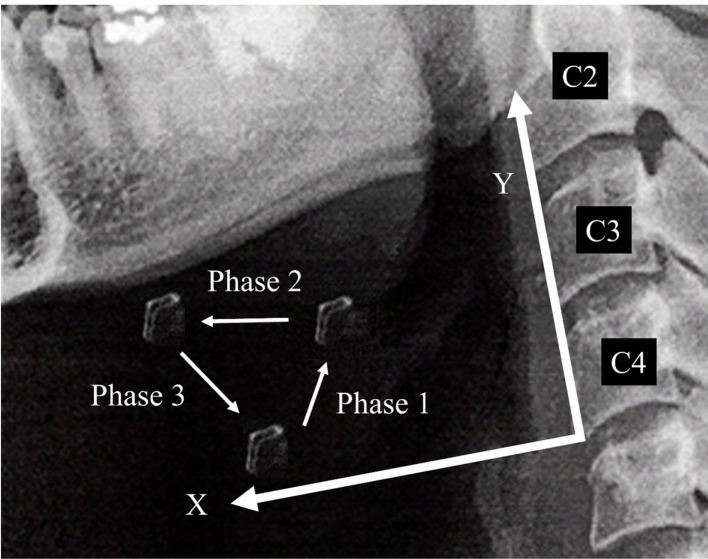

We retrospectively analyzed the data from 66 patients who underwent VFSS between April 2019 and December 2019. Hyoid bone movement was classified into three phases: upward, forward, and downward. We measured the velocity and distance of hyoid bone movement in each phase, as well as the pharyngeal residue after swallowing. The correlation between hyoid bone movement and the amount of pharyngeal residue was analyzed using Spearman's rank correlation coefficient. A receiver operating characteristic (ROC) analysis was performed to evaluate the presence of pyriform sinus residue.

Hyoid bone velocity and distance during the forward phase correlated with the amount of pyriform sinus residue (velocity: r=0.311, P=0.011; distance: r=0.255, P=0.0389). ROC analysis revealed that the cutoff value for hyoid bone velocity during the forward phase was 26.1 mm/s (0.846 sensitivity, 0.604 specificity) with an area under the curve of 0.717.

The velocity and distance of the hyoid bone during the forward phase were significantly related to the amount of pyriform sinus residue. In VFSS assessment, it is important to classify hyoid bone movement into three phases-upward, forward, and downward-and to calculate its velocity and distance.